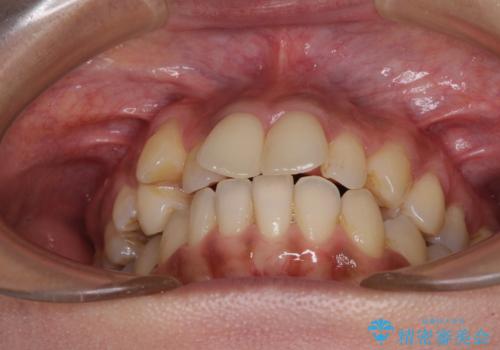

- 八重歯と上下前歯のでこぼこを気にして来院された患者様です。

上下前歯部叢生のスペース獲得のため、上下顎左右小臼歯各1歯(計4本)を抜歯して、ワイヤー装置にて矯正治療を行うこととしました。

上下の正中位置が大きくずれていたため、上下正中が合わないまま終了することが予想されましたが、思っていた以上にスムーズに歯が移動し、満足いただける仕上がりとなりました。